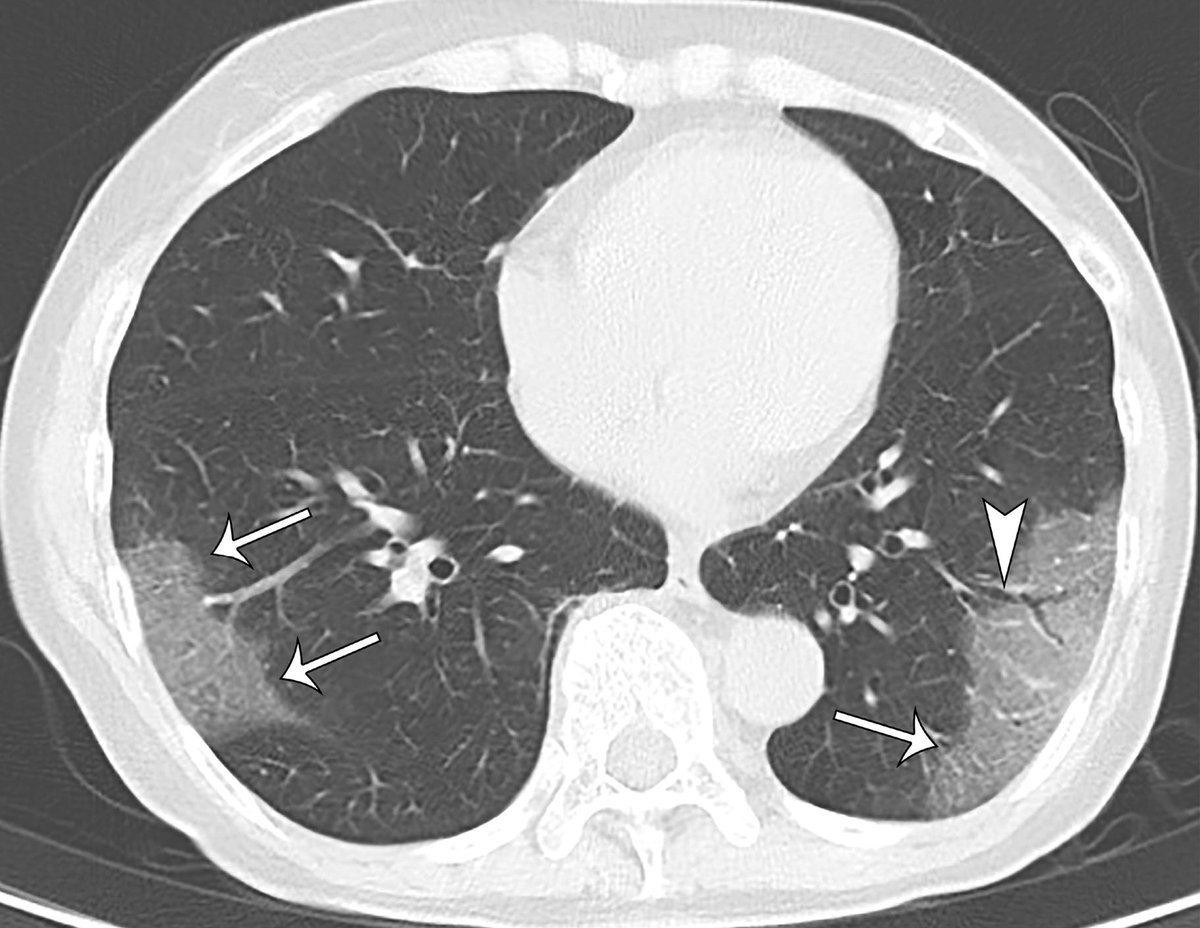

Поражение легких является одним из основных симптомов коронавируса (COVID-19). В данной статье представлены фото рентгеновских снимков, которые позволяют визуально оценить состояние легких при этом заболевании.

На фотографиях рентгеновских снимков видно, как вирус воздействует на легочную ткань. Характерные признаки поражения легких включают пятна, инфильтраты и наличие жидкости внутри легочных альвеол.

Фото рентгеновских снимков помогают врачам и специалистам визуально определить степень поражения легких и принять соответствующие меры лечения и поддержки пациента.